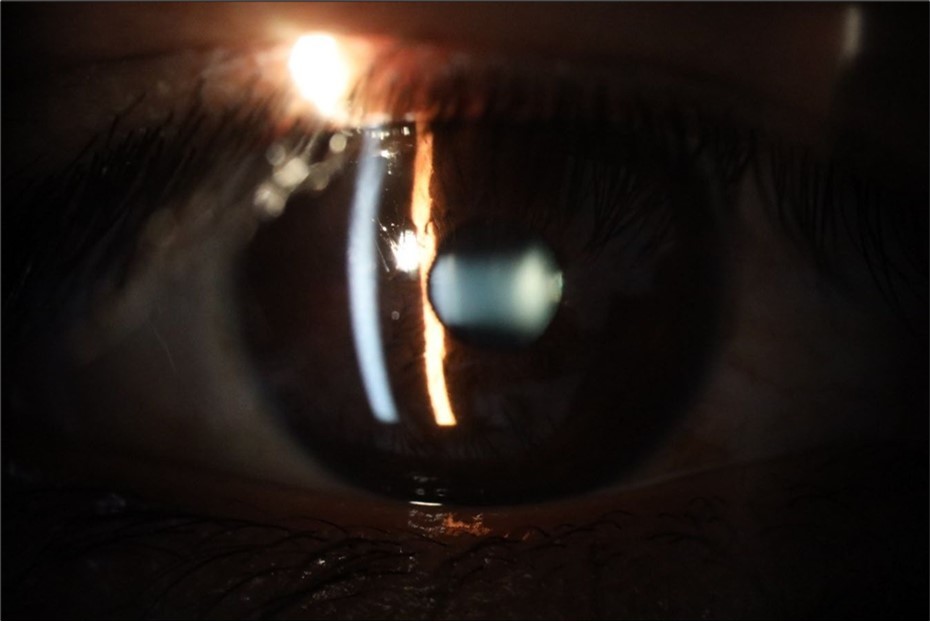

Figure 25.Mirror reflection of the affected eye (right side), with good appearance. This indicates that the transparent media of the eyeball (Cornea, anterior chamber, lens, and vitreous) are in good condition.

Figure 26.The macrograph of the anterior segment of the right eye (affected) shows very good transparency of the cornea, anterior chamber, lens, and vitreous.

Heart beat: 65 x´

Sciascopy: ++/++